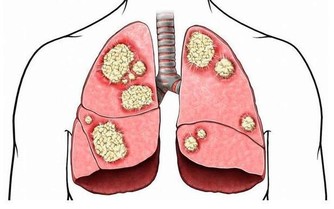

事實上,脂肪肝會導致更嚴重並且常常是致命的肝臟疾病,包括肝癌。肝病的主要階段包括單純性脂肪肝(脂肪變性)、纖維化和最嚴重的階段,也就是肝硬化,它可以導致肝功能衰竭和肝癌。

除了最可怕的癌症,以及陰魂不散的糖尿病、高血壓、高膽固醇都是脂肪肝可能帶來的風險。那麼,哪些人群是脂肪肝的高危人群呢?

然而,當病情變得更加嚴重時,會導致腹痛、疲勞、極度疲倦、不明原因的體重減輕和虛弱。如果肝硬化發展,患者可能出現嚴重症狀,比如皮膚和眼白色變黃,腿部、腳踝、腳或肚子腫脹。然而等到那時候,就已經太晚了。